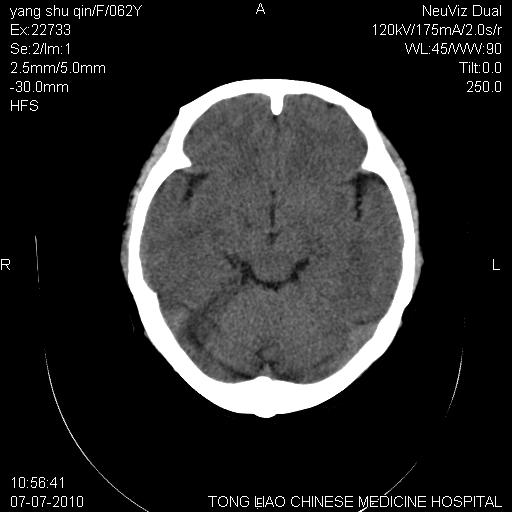

第二例  头晕,头痛

都是单侧小脑半球出现片状低密度灶,可以诊断脑萎缩吗?还是小脑梗塞?

局限性脑萎缩,未见明显梗死灶

小脑萎缩。

两例病人都未见没显异常,我的老师曾经说过,对一些老年性改变,跟此次发病临床表现无关的东西,只描述不结论,扣了帽子反而加重病人思想负担!